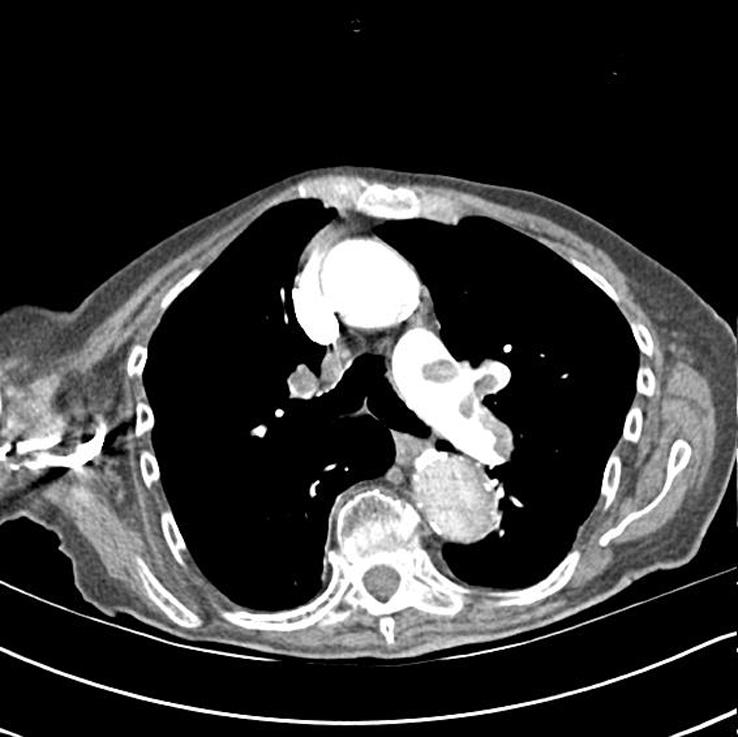

Figure 1.

Computed tomographic pulmonary angiogram showing pulmonary emboli. The patient, an 85 year old woman, presented with sudden onset breathlessness and pleuritic pain, three weeks after surgery for a fractured neck of femur. She received anticoagulation treatment with warfarin and made a full recovery